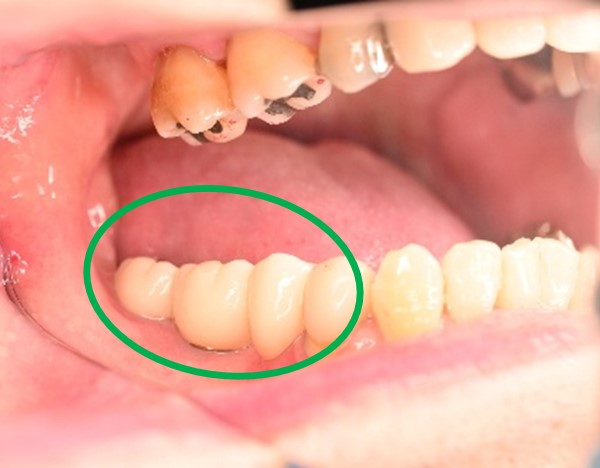

男性Kさん 60代(インプラント)

主訴

下の左右歯がないところに歯を入れたい。

治療内容

左右それぞれ3本歯がないところに2本ずつインプラントを埋入しました。

所感

上と下の歯の咬合接触がないすれ違い咬合です。上下義歯で対応するには最も難しいタイプの欠損状況です。治療開始前は、上下部分入れ歯が入っていましたが、入れ歯の安定が悪く、あちこちの歯茎に入れ歯が当たって痛く、満足に噛める状態ではありませんでした。上顎は、残ってる歯を活用するマグネット式総義歯を、下顎はインプラントを提案しました。上顎は、現在残っている歯の根管治療中です。上顎にマグネット式総義歯がはいれば、何でも食べられるようになります。

インプラント4本:¥363,000×4本=¥1,452,000(税込)

ポンティック2本:¥115,500×2本=¥231,000(税込)

合計:¥1,683,000(税込)

Before

▼初診時に使用していた部分入れ歯を装着したところ

▼インプラント埋入前

After

▼インプラント埋入後